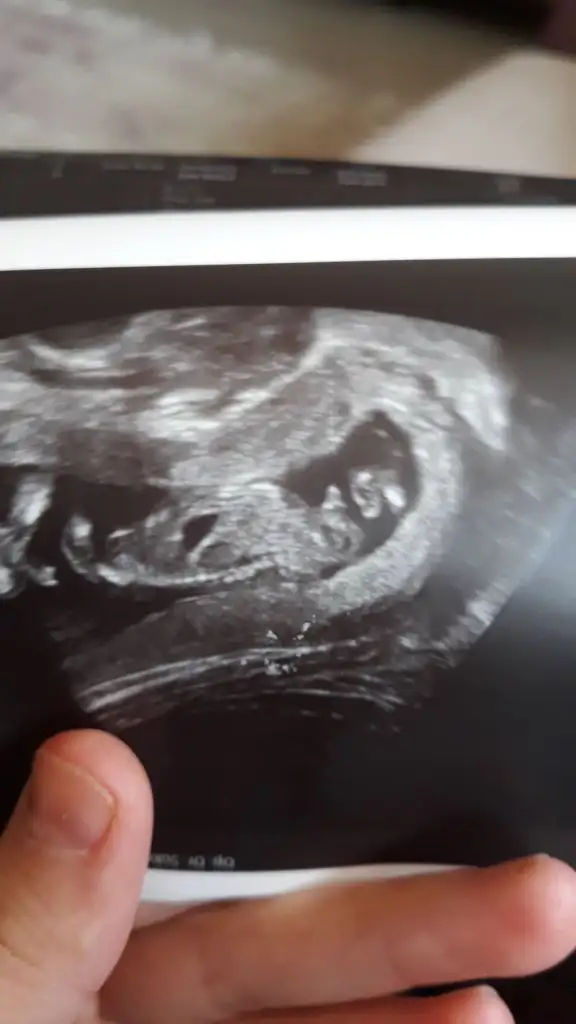

Cnm ayna gibi usg hep yüsütüydü asla kıpırdamadı neden dedim uyuyor dedi banada hiç bilgi vermez vermedi direk kız dedi kesin mi dedim kesin dedi, sinir oldum insan bir uyandırır zorlar falan 10dk bakmadı ama fotoda kız gibi yinede 20yi bekliyorum düzgün göreyim anlatsın bi doktorda ya bak fotolarıma, şu son fotoda bacak arası gözüküyor ama emin olamıyorum çünkü göstermedi doktor şurası şu diyeYüz üstü olduğunu nerden anlıyorsun canım. Ben hiçbirşey anlamıyorum ya. Doktor da demiyor şu pozisyonda becak arası şu organ var eli şu kolu şu. Son gittiğimdeki doktor söyledi sadece o da 2 dakika baktı bakmadı kalktım.

Hngisiymiş pipiKizlar beni bile tereddutte biraktirdiniz cinsiyet konusunda aksam aksam ultrasyon resmine baktimdegisirmi bilemiyorum artik ayrintiliya daha var doktor pipisi bu dedi sag tarafa bakin

Hngisiymiş pipianlamadım çizsene

Kiz kafasi obur taraftaOrası baban kafasının yanında kolları gibi geldi ama doktor dediyse doğrudur

Kiz kafasi obur taraftabu alt bolumu bacak arasiymis orasi degisirmi dedim bak simdi burda gorunen degisirmi dedi. Bilemedim artik

yav ben anlayamıyorum bende kafa popo net sadece yüzüstü böle görünce anlamıyom ozaman doğrudur